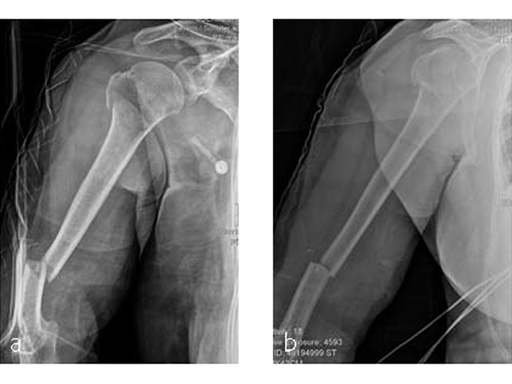

Case 4: AO 12C1 fracture following fall

A 54-year-old woman, and otherwise healthy patient, fell during her holidays and sustained an AO 12C1 fracture. There was no major soft tissue trauma. Other lesions: avulsion at the 5th metatarsal base, and concussion. Surgery took place on day 9 after the accident. The patient left the hospital the day after surgery.

Case 5: Staircase fall

Following a fall downstairs, a 70-year-old woman sustained a head injury with intracerebral and subdural haematoma, as well as a complex fracture of the right humerus, representing a minimal displaced proximal and an oblique fracture in the distal part of the humerus (Fig 11).